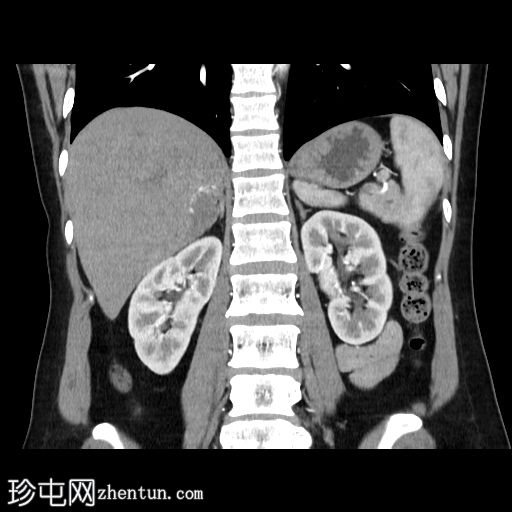

5.jpg

冠状面

非造影

在轴向、冠状面和矢状面上均可见肝5/6段病变。动脉期可见周围结节状强化,门静脉期可见进行性向心性充盈,延迟期亦持续存在。这些表现为肝血管瘤的特征性表现。

然而,目前的CT扫描显示动脉期呈周围结节性强化,门静脉期呈进行性向心性充盈,且延迟成像后仍持续存在。这些特征是肝血管瘤的特征。未发现其他肝脏病变。